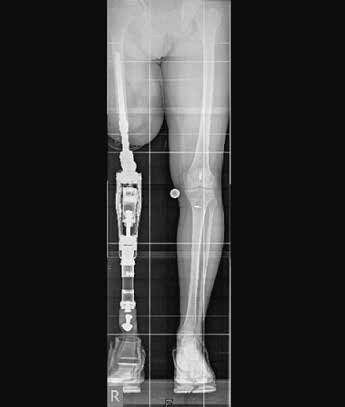

Seit über 10 Jahren gibt es in Deutschland eine mittlerweile auf langjähriger Erfahrung basierende alternative Versorgungsmöglichkeit zur Schaftprothese nach Ober- und Unterschenkelamputation. Dabei handelt es sich um die sogenannte Endo-Exo-Versorgung, eine den Restknochen als Verankerung nutzende operative Herangehensweise. In einem zweigeteilten chirurgischen Verfahren wird der Prothesenstiel zunächst in den Knochen eingebracht und die Haut im Anschluss wieder verschlossen. Nach einer Einheilungszeit (Osseointegration) von ca. 6 Wochen wird dann während eines zweiten Eingriffs ein sogenanntes Stoma geschaffen, welches dazu dient, ein Brückenmodul an das im Knochen liegende Implantat anzudocken und nach außen zu leiten. An dieses Modul kann dann die äußere Prothetik mitsamt künstlichen Knie- bzw. Fußgelenken angebracht werden. Die dem Verfahren innewohnende stabile Verbindung von Körper und Prothese sowie der anatomiegerechte Wiederaufbau der Körperachse hat dabei die Überwindung der o. g. Schaftprothesenproblematik zum Ziel und soll den Betroffenen ein Leben möglichst nahe dem eines Unbeeinträchtigten ermöglichen (Abb. 1).

Herr M. S., geb. 1971, hat sich im März 2010 dem ersten Schritt der Operation unterzogen und war davor über 19 Jahre hinweg mit Schaftprothesen versorgt. Dabei erinnert er sich vor allem an die beschwerlich „lange(n) Wege zur Anpassung von Probeschäften bzw. Schäften” und die immer wieder auftretenden Volumenschwankungen des Stumpfes „durch den Abbau der Muskulatur”, was einen korrekten Sitz der Schäfte über längere Zeit vereitelte. Zudem habe er „häufig Haarwurzelentzündungen gehabt”, die durch den Druck der Köcher zustande kamen. Herr M. begrüßt vor allem den durch die Endo-Exo-Prothese „wieder zunehmende(n) Muskelaufbau” des Reststumpfes. Aufgrund einer Läsion des Plexus brachialis mit partieller Lähmung des rechten Arms und der rechten Hand ist Herr M. zwar zusätzlich gehandicapt, jedoch kann er die Endo-Exo-Prothese leicht und selbstständig an- und wieder abbauen, da hierfür nur zwei Schrauben betätigt werden müssen (Abb. 2). Insgesamt sei die Prothese „sehr viel bequemer” für ihn, auch wenn er manchmal Verschleißprobleme mit den äußeren Adaptern gehabt habe. Bei Herrn M. kam es nach einem Sturz zu einer pertrochantären Femurfraktur proximal des Implantates. Er konnte daraufhin mit einem der dynamischen Hüftschraube ähnelnden Osteosynthesemodul versorgt werden, ist seit dem Sturz aber sehr viel vorsichtiger und vermeidet Rotationsbelastungen. Dennoch hat er seit der Versorgung einen Tauchschein gemacht und fährt Fahrrad.